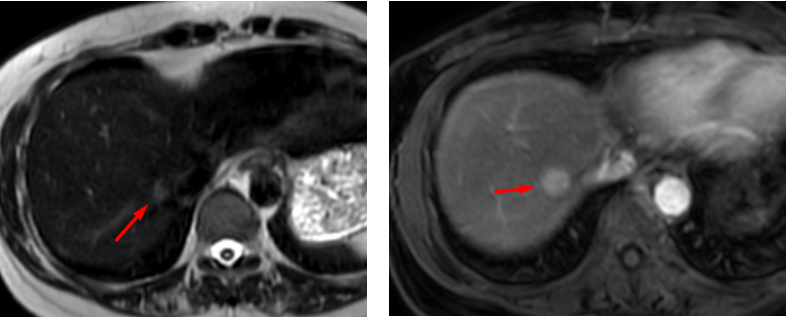

Indeterminate liver lesion on conventional MRI

Liver lesion demonstrating retention of hepatocyte-specific contrast agent in the hepatobiliary phase, suggestive of focal nodular hyperplasia (FNH).